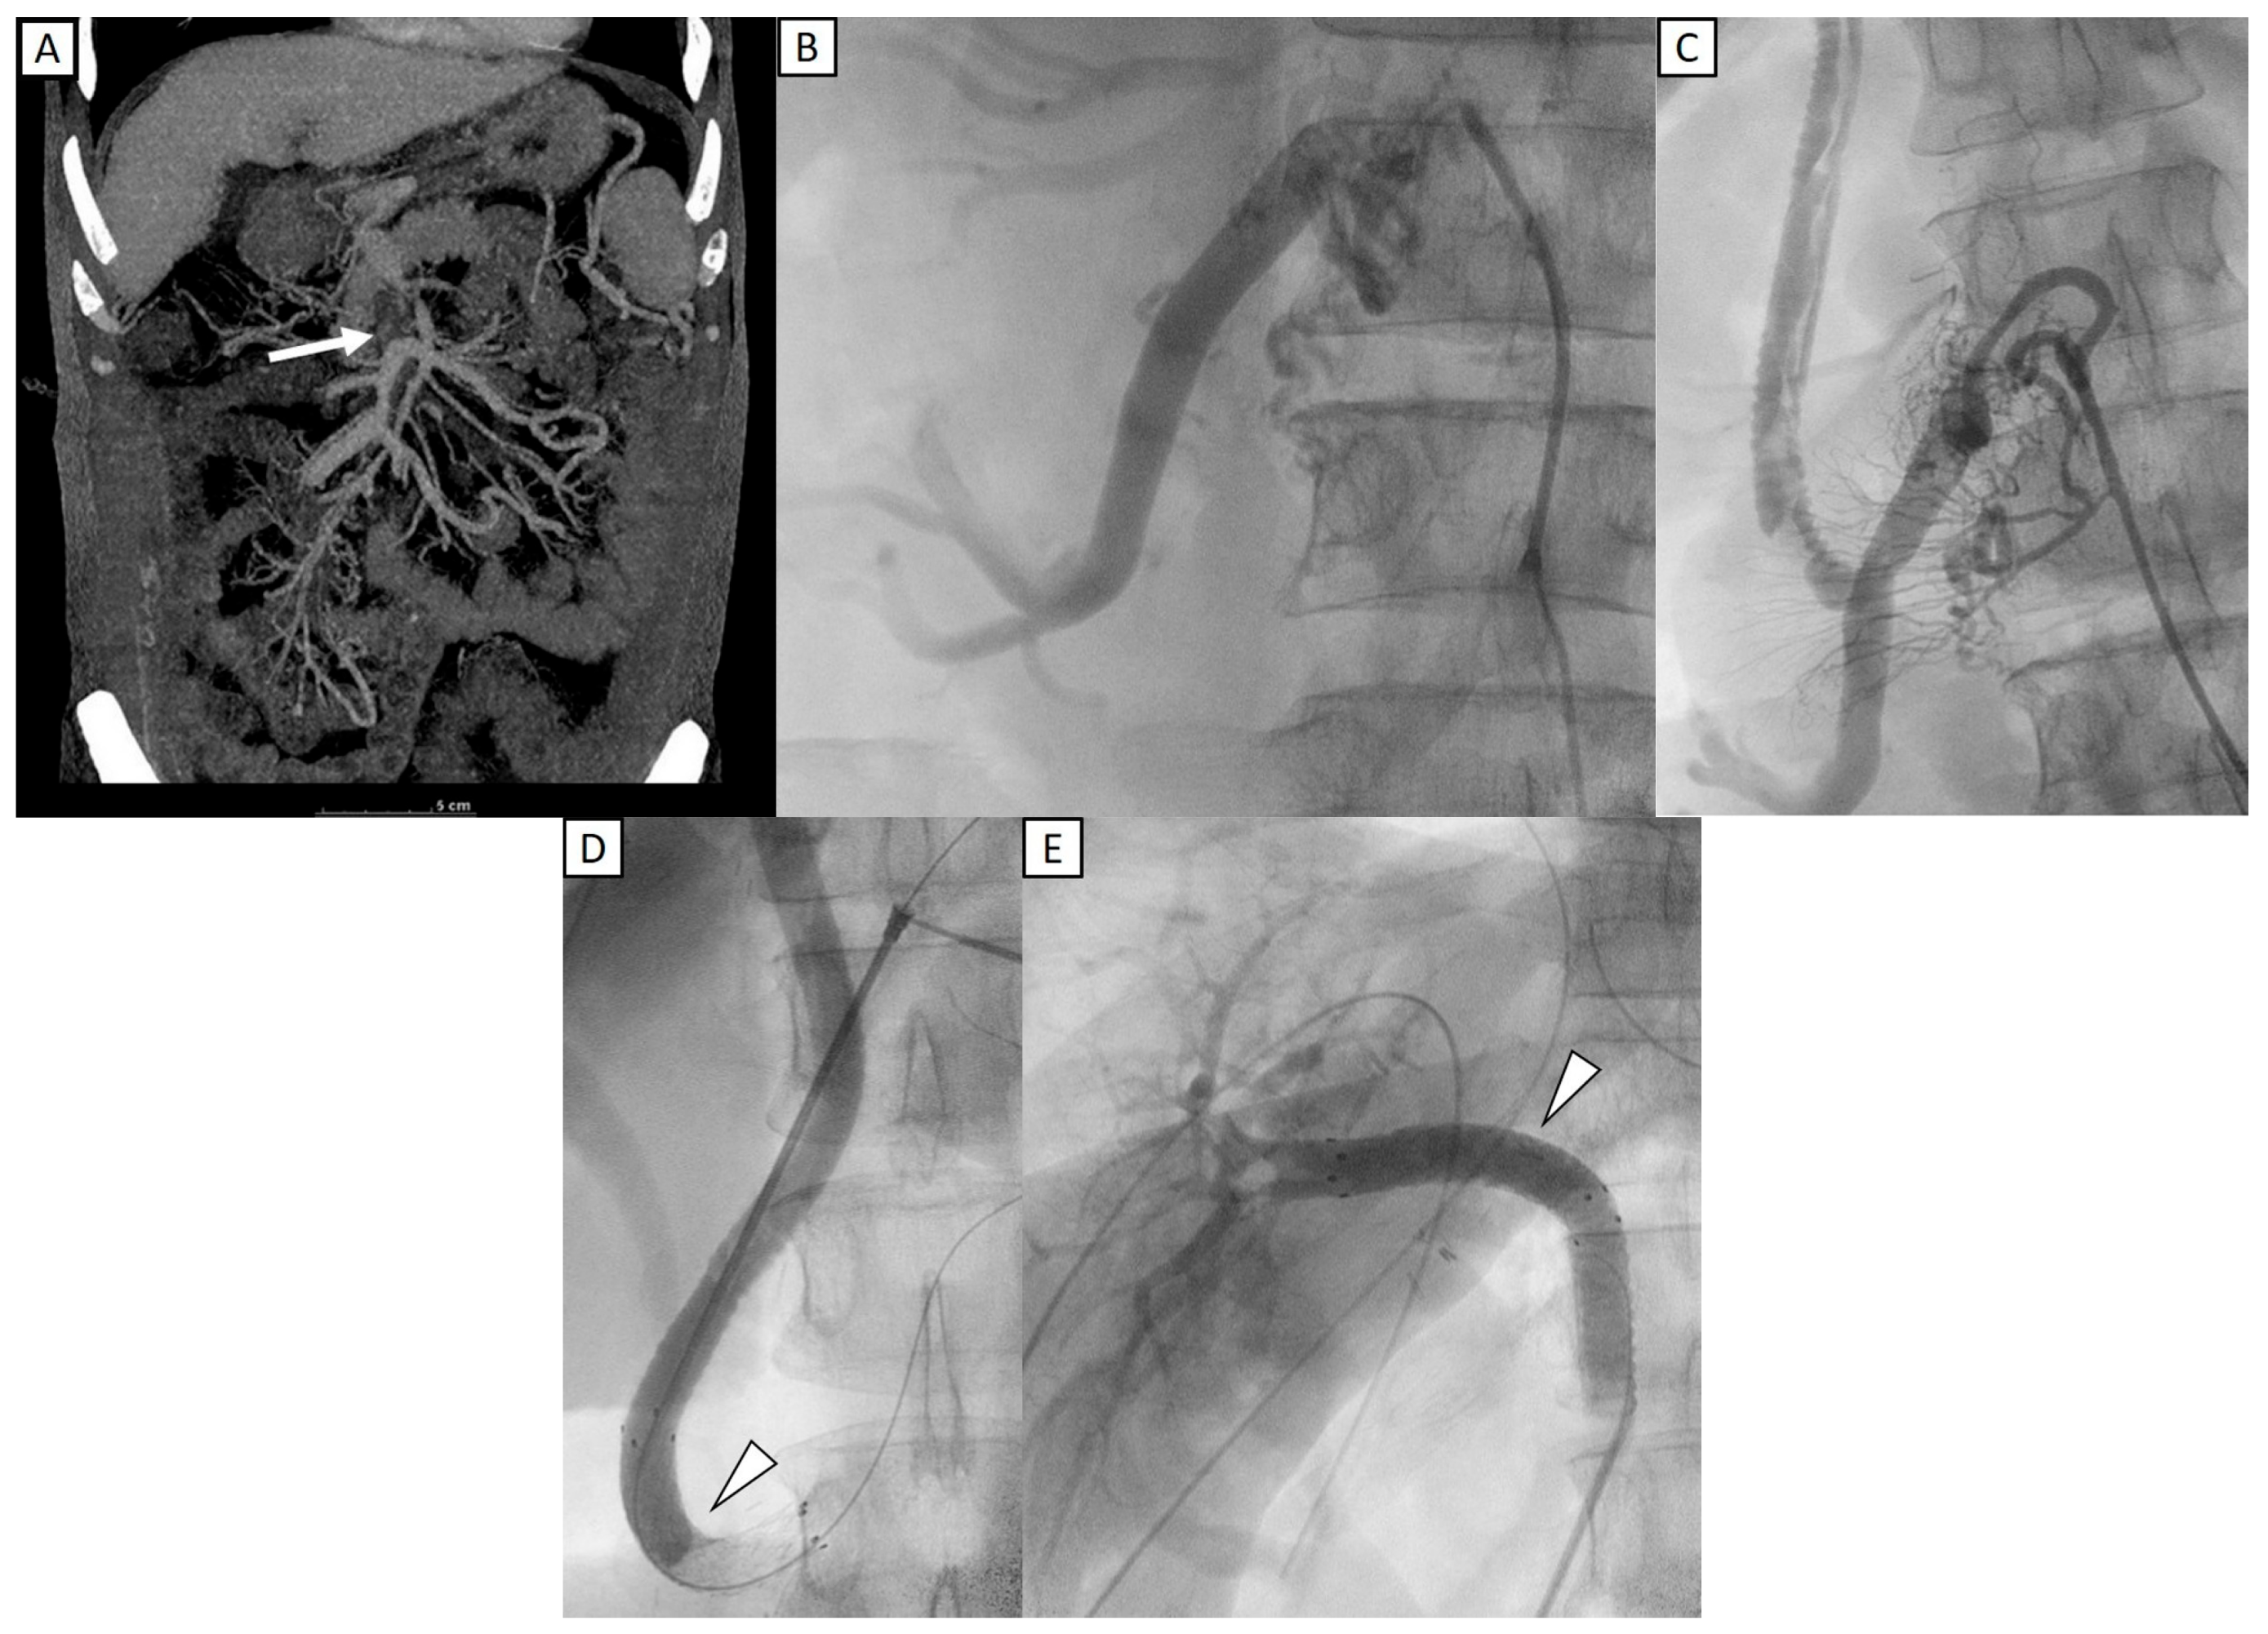

Figure 2 shows a 48-year-old man who underwent liver transplantation. Preoperative CT imaging revealed thrombosis of the superior mesenteric vein (SMV), partial thrombosis of the main portal vein (MPV), dilated coronary veins, and an extrahepatic shunt originating from an engorged ileocolic vein. IOPV confirmed complete occlusion of the distal SMV and portal vein, with a large ileocolic vein. To reconstruct the portal vein, a long interposition graft with Gelsoft (10 mm, 25 cm) (Terumo, Tokyo, Japan) was placed from the ileocolic vein to the grafted right portal vein [19]. To optimize portal inflow, the distal end of the ileocolic vein was ligated. The follow-up IOPV demonstrated portal vein patency; however, multiple thrombi were identified within the interposition graft. Consequently, thrombectomy was performed, followed by venoplasty and stent placement. Two stents were deployed—one extending from the ileocolic vein to the interposition graft and the other from the interposition graft to the grafted right portal vein. Portal venography confirmed restored patency of both the interposition graft and the portal vein. Subsequent Doppler ultrasound evaluation demonstrated adequate portal perfusion, with a measured portal vein flow velocity of 32.1 cm/s.

Portal vein flow velocity increased significantly following IOPV and the corresponding interventions, underscoring their effectiveness in restoring sufficient portal inflow, a critical factor for graft regeneration and function. Adequate inflow was achieved in 32 patients, while 2 continued to exhibit low or occluded flow despite intervention. Both of these patients had IOPV performed post-transplant and presented with severe adhesions, complicating the effectiveness of intervention. One patient presented with multiple large portosystemic shunts, including portal-renal and portal-retroperitoneal shunts. Despite shunt clamping, venography revealed that the portal vein was not directly visualized; however, a prominent collateral branch from the superior mesenteric vein to the choledochal vein was identified, demonstrating good intrahepatic inflow. Consequently, a portal-renal shunt ligation was performed to redirect blood flow. The second patient exhibited significant portal vein stenosis, managed with stent placement and coronary variceal occlusion using a vascular plug [20]. Although portal flow initially improved, follow-up US showed relatively low portal inflow, probably due to extensive portosystemic collateralization and refractory shunting. These cases underscore the challenges of severe shunting and the need for further refinement in additional therapeutic strategies to enhance outcomes in similar clinical scenarios. As illustrated in Figure 2, this case highlights the complexity of managing extensive venous thrombosis in liver transplantation and underscores the role of IOPV in guiding intraoperative vascular reconstruction and optimizing hemodynamic outcomes [21].

Figure 2. A 48-year-old man who underwent liver transplantation. (A) Preoperative CT imaging revealed total occlusion of portal vein with thrombosis of the superior mesenteric vein (SMV) (white arrow). (B) IOPV through the mesenteric vein confirmed complete occlusion of the distal SMV, with no flow to portal vein, and with a large ileocolic vein. (C) An interposition graft with Gelsoft (10 mm, 25 cm) (Terumo, Tokyo, Japan) was placed from the ileocolic vein to the grafted right portal vein. Multiple filling defects were identified within the interposition graft, favoring thrombi. (D,E) Two stents (12 mm × 60 mm) (E-Luminexx, Bard Peripheral Vascular, Tempe, AZ, USA) were deployed, with one extending from ileocolic vein to the interposition graft and another from the interposition graft to the grafted right portal vein (arrowhead). Post stenting portal venography confirmed patency of the interposition graft and portal vein.